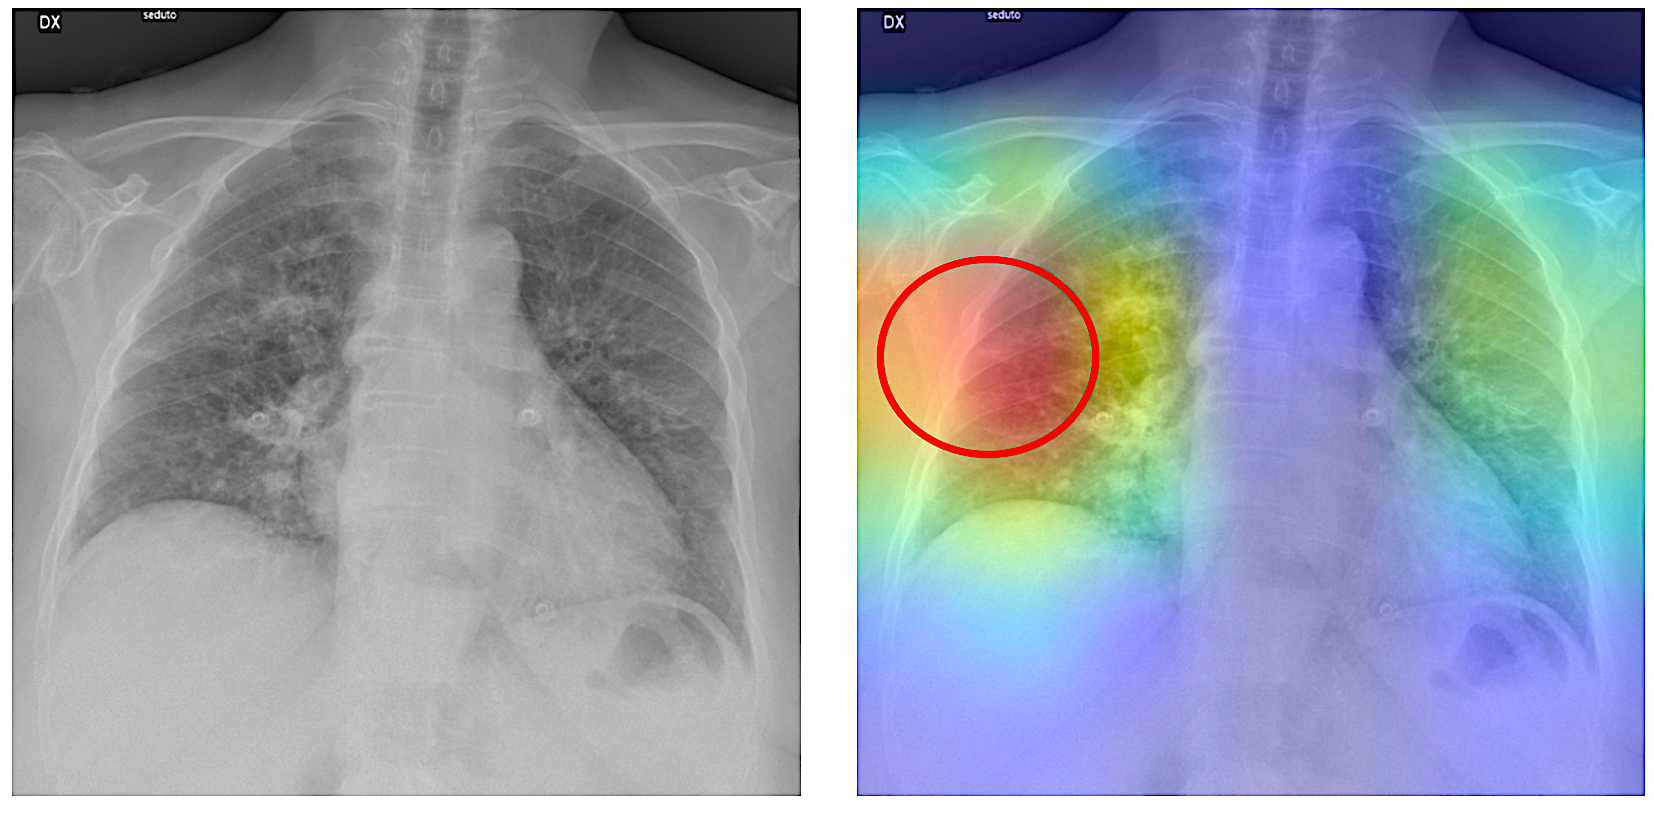

In early tests, the duo’s new AI-powered prediction system (known as RAIDER, for Rapid AI Diagnosis at Edge using Ensemble Models for Radiology) has proven highly accurate at flagging both COVID and pneumonia cases from X-rays. It’s also compact, produces rapid diagnoses and doesn’t use much power.

“We believe this model could help physicians quickly identify and diagnose both known and newly emerging respiratory diseases from chest radiographs,” says Wang, “providing high precision with minimal system requirements.”

“We were surprised by the high accuracy and low latency. The two learning networks in this small pilot study proved to be 97% to 98% accurate at diagnosing COVID-19 and viral pneumonia,” explains Wang. “That’s far better than the 60% to 70%, for example, accuracy of PCR testing for COVID.”